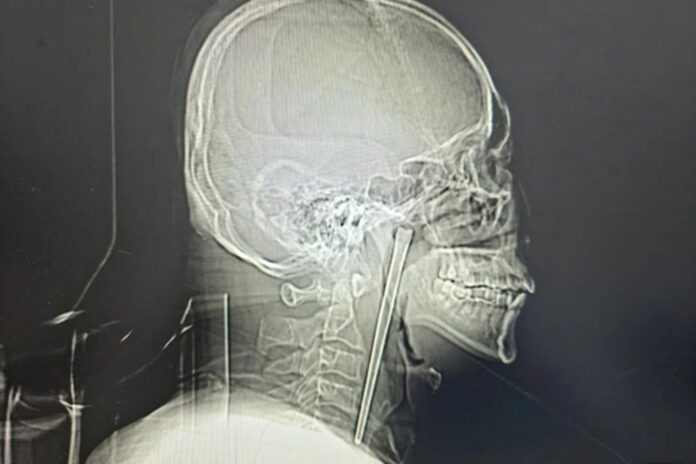

A drunk man in China swallowed a metal chopstick while eating dinner eight years ago — and decided to leave it lodged in his throat until a surgeon finally yanked it out last month, according to a jaw-dropping report.

The “alcoholic” patient, identified only as Mr. Wang, went in for a check-up shortly after gulping down the five-inch utensil in 2018 but refused to have it removed, according to a hospital case study published in March.

Wang, 46, didn’t want doctors to cut his neck open at the time, so he lived with the oddity — and discomfort for years, the South China Morning Post reported.

Surgeons performed a minimally invasive operation to remove the obstructive object via Wang’s mouth instead of slicing open his neck, according to the hospital’s report.